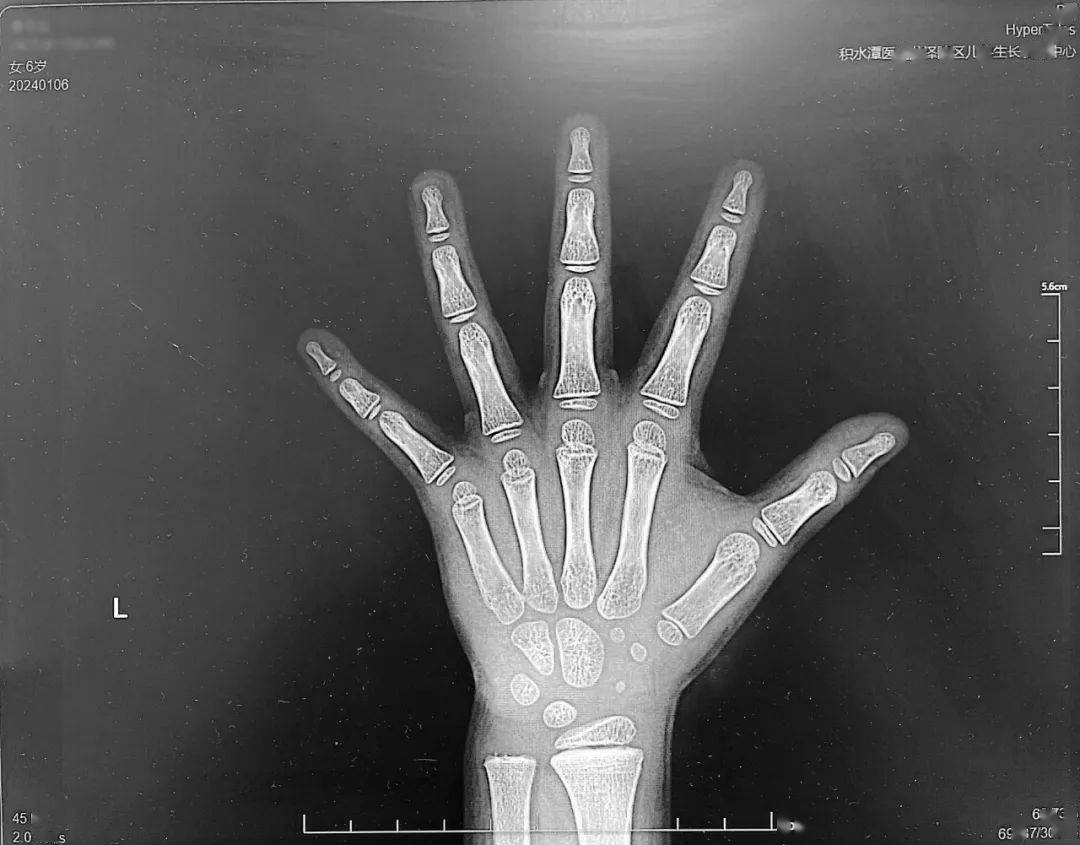

骨龄(Bone Age,BA):骨骼年龄能够更准确地评估及预测身高,通过评估X线摄影所示手骨和腕骨的外观及形状而获知骨龄,皮皮的骨龄结果约为5.5岁(如图1),骨龄对应的生长曲线为图3,所对应的成人期最终身高更有参考价值,更接近其遗 传靶身高。但是,单次骨龄的结果只能反映该检测时间节点的发育状况,据此预测未来身高并不科学。尤其在具体评估某一个体青春期的生长或成熟的平衡时,应考虑性别、父母身高、发育年龄、性发育状态及进展速度、既往生长速度(包括青春期前及青春发 动后)以及骨龄和体格发育的动态变化等综合因素。骨龄的动态评估对身高的预测更重要。

图1:x光片显示皮皮的骨龄为5.5岁